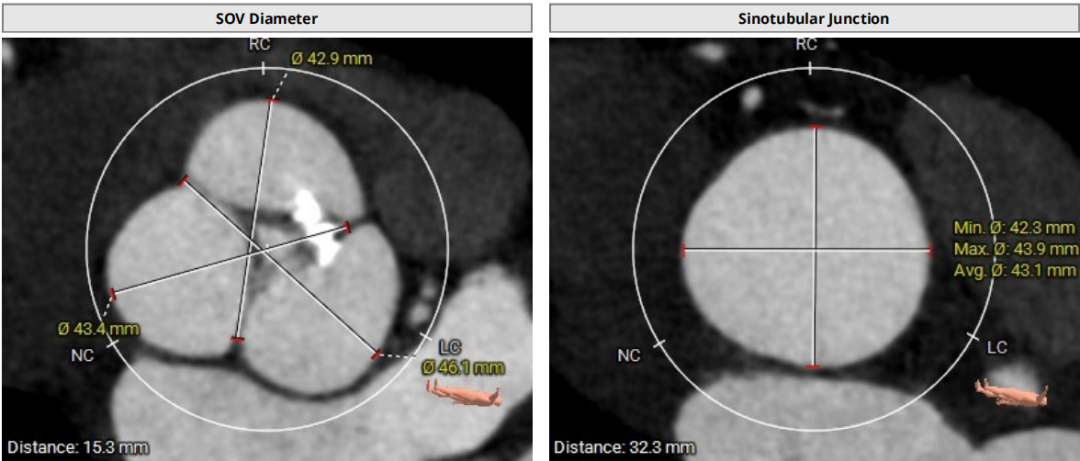

术前CT评估示

三叶瓣,瓣环面积约578.0mm²,折算瓣环直径27.1mm,LVOT约618.8mm²,折算直径28.1mm,SOV:46.1*42.9*43.4mm,窦部空间较大,瓣叶长度适中,瓣叶明显增厚,STJ:32.3(H)* 43.1mm (D),STJ直径和高度足够;LCA:22.6mm,RCA:22.9mm,瓣叶长度适中,窦部空间足够;瓣环夹角53°。

模拟29mm瓣膜植入情况: